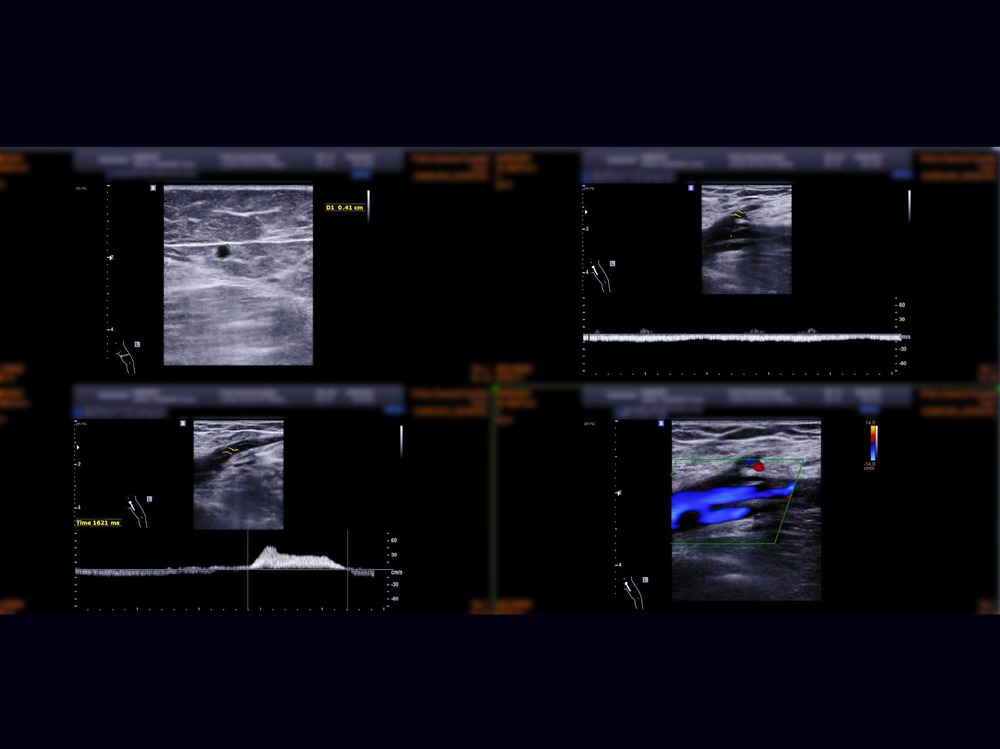

A Deep Vein Thrombosis scan is a non-invasive medical diagnostic imaging to check the presence of thrombus (blood clots) and blood flow in the large veins in the arms or legs. This scan also looks at superficial veins in the arms or legs if there are any blockage due to blood clots. However, the occurrence of blood clots is more common in the legs. This scan includes the assessment of femoral veins, sapheno-femoral junction, popliteal veins, sapheno-popliteal junction, and calf veins in your legs. It can help your healthcare professional to determine an immediate treatment in various conditions in your peripheral veins.

A Deep Vein Doppler ultrasound is a non-invasive medical diagnostic imaging to check the presence of thrombus (blood clots) and blood flow in the large veins in the arms or legs. This scan also looks at superficial veins in the arms or legs if there are any blockage due to blood clots. However, the occurrence of blood clots is more common in the legs. This scan includes the assessment of femoral veins, sapheno-femoral junction, popliteal veins, sapheno-popliteal junction, and calf veins in your legs. It can help your healthcare professional to determine an immediate treatment in various conditions in your peripheral veins.

The blood clots can be a medical emergency as they can reach into the lungs and can cause pulmonary embolism which can be life threating.

The most common conditions of the deep veins in the arms or legs can be thrombus in deep vein.

Thrombophlebitis.